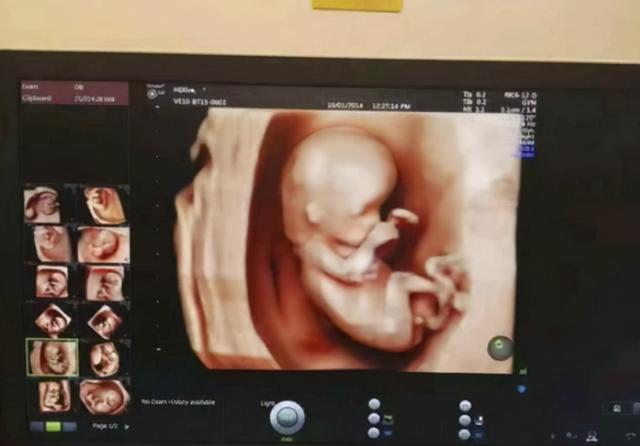

怀孕最初的几周,大家被孕吐困扰着,接着在各种产检中折腾来折腾去,部分准妈妈开始焦虑和不安。进入孕期的28周,也意味着迈过了孕期的一个分界线。

进入孕28周,准妈妈正式迎来孕晚期,肚子越来越重,需要格外注意的事情也有所变化。

理性分析汪女士婆婆说的话,28周的胎儿身体发育确实越来越成熟,包括一些畸形的检查也都通过了。

进入孕晚期后,胎儿的个头越来越大,从前能在妈妈肚子里任意翻身,但孕晚活动空间小,想动却动弹不得。